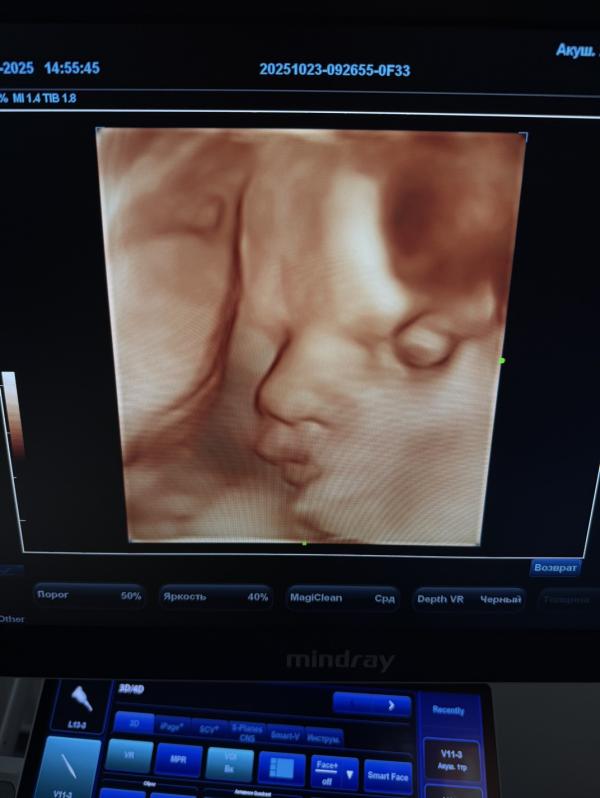

Беременность на фоне приёма противозачаточных Силуэт

Беременность наступила на фоне приема притивозачаточного Силуэт

Очень редкий случай , но такое тоже возможно

Кажется , единственный 100% метод контрацепции это воздержание 😆